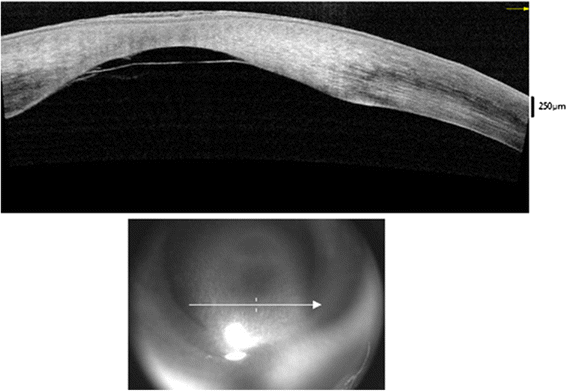

B. keratoconus posticus circumscriptus

국소적 함몰로 경계가 뚜렷하게 되며,

각막 후면의 함요가 보입니다.

이경우는 기질의흉터가 동반됩니다